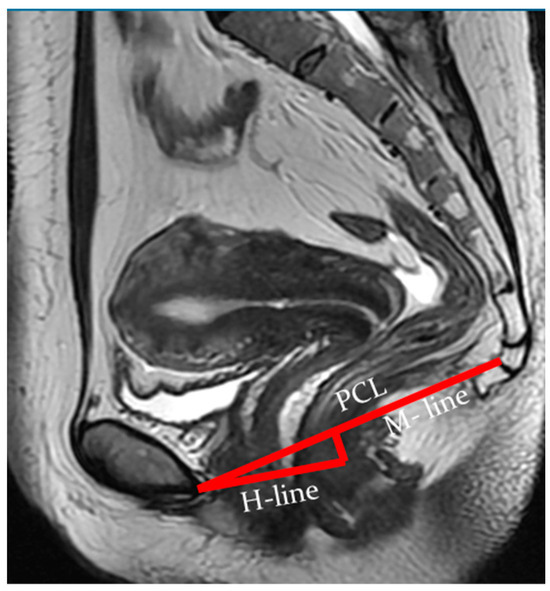

Indicators of the condition of the pelvic organs are assessed in relation to the PCL, connecting the lower edge of the pubic symphysis with the last coccygeal junction; the H line—the line connecting the lower edge of the pubic symphysis with the posterior wall of the anorectal junction, which corresponds to the urogenital slit, and its sagittal size must not exceed 5 cm; and the M line—the perpendicular connecting the H line with the PCL, which must not exceed 2 cm (Figure 3).

Figure 3. Assessment of pelvic organ parameters in relation to PCL and H and M lines.